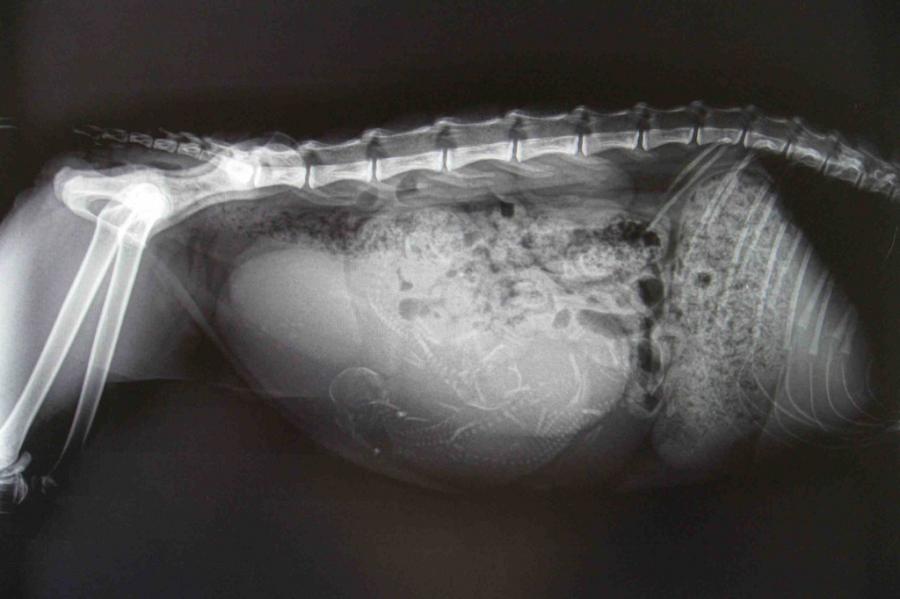

Une radiographie est recommandée entre 50 et 55 jours car c’est le moment idéal pour compter les bébés  et pour savoir s’ils passeront bien au niveau du bassin.